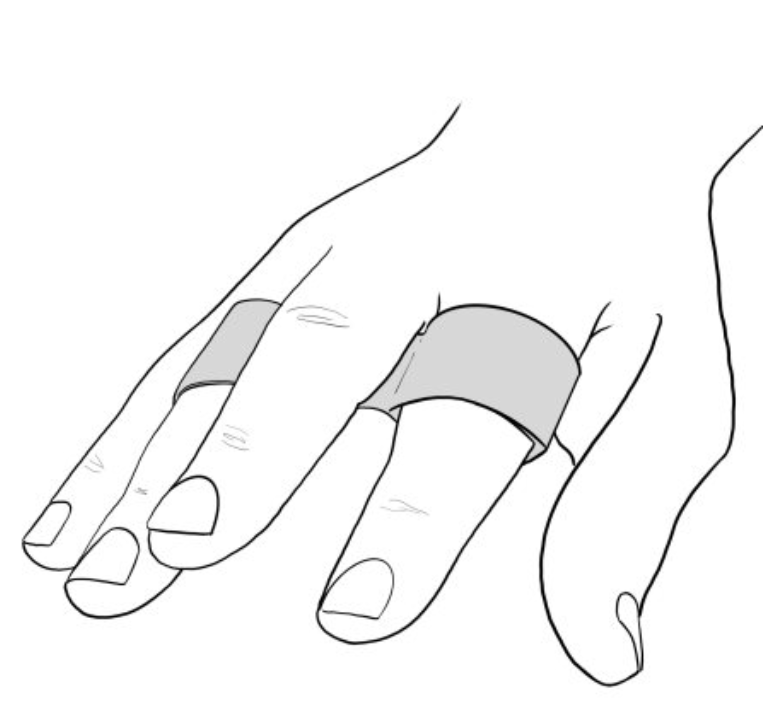

一项前瞻性随机试验,比较第五掌骨颈骨折患者的 Buddy Taping 与闭合复位和石膏固定的功能结果

作者:Rachel Reed Martínez-Catalán, N.、Pajares, S.、Llanos, L.、Mahillo, I. 和 Calvo, E. (2020)。一项前瞻性随机试验,比较 Buddy 的功能结果......